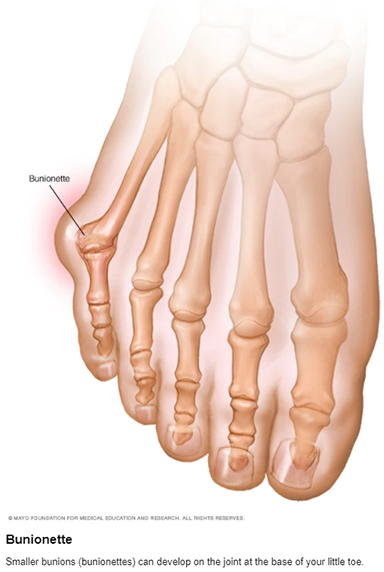

Bunions

A bunion is a bony bump that forms on the joint at the base of your big toe. It occurs when some of the bones in the front part of your foot move out of place. This causes the tip of your big toe to get pulled toward the smaller toes and forces the joint at the base of your big toe to stick out. The skin over the bunion might be red and sore.

A bunion is a bony bump that forms on the joint at the base of your big toe. It occurs when some of the bones in the front part of your foot move out of place. This causes the tip of your big toe to get pulled toward the smaller toes and forces the joint at the base of your big toe to stick out. The skin over the bunion might be red and sore.

Wearing tight, narrow shoes might cause bunions or make them worse. Bunions can also develop as a result of the shape of your foot, a foot deformity or a medical condition, such as arthritis.

Smaller bunions (bunionettes) can develop on the joint of your little toe.